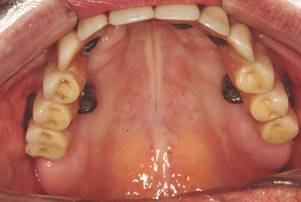

Fenestration of alveolar mucosa

Because of the cases with severe alveolar resorption, including in the maxillary zygomatic pillar, the fenestration of the alveolar mucosa may occur, creating a retraction of the mucosa and exposure thread of the implant (Fig. 3). If it is possible, the fixation must be maintained inside the maxillary sinus, preserving the zygomatic process, an important anatomic repair to the treatment of complications and loss of zygomatic implants. This detail is more important when the patient presents a ridge with a little loss in height, because the muscle insertion of deep sulcus is farthest, resulting in gingival retractions. In cases of maxillary atrophy, where the muscle insertion is maintained close of the ridge, the fenestrations are protected, as in mutilated patients without alveolar portion and the implant is placed with great fenestration. The treatment of this late complication is impracticable and the biggest difficulty is to control the bacterial plaque, which is more difficult than in conventional situations. It is noteworthy the importance of certifying the absence of BSC and periodic follow-up should be done to evaluate the periimplant condition.